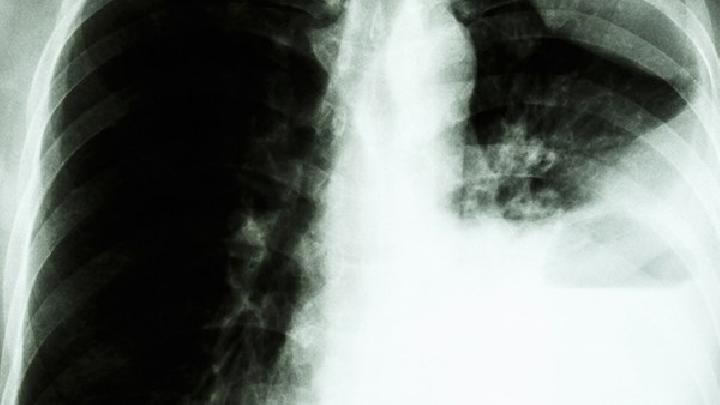

為什么肺癌不傳染?

首先,我們應該知道肺癌是一種癌癥,它是否是一種傳染病,它是否會被感染,然后我們應該找出癌癥是否會被感染。這個問題早就被提出了,并進行了大量的觀察和研究。